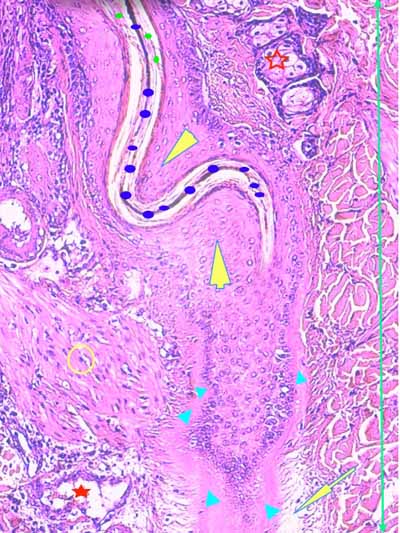

Biopsies cutanées

Sur l’une des biopsies, l’épiderme et les structures annexielles sont nécrosées ainsi que de larges plages de fibres de collagène dans le derme profond (Fig6). Dans le derme périannexiel, on observe une discrète hypercellularité diffuse sous la forme de cellules pycnotiques (Fig2,3,13,14). En profondeur, dans l’hypoderme, on observe une dilacération des septa conjonctifs interlobulaires et des adipocytes par un matériel sérofibrineux, parsemé d’une poussière nucléaire entourant parfois des structures vasculaires, artériolaires et veineuses, de moyen calibre dont la lumière est occupée par un thrombi fibrineux et dont les cellules endothéliales apparaissent vacuolisées (Fig7,8,9). Sur les autres biopsies, l’épiderme montre des lésions de dégénérescence réticulaire (Fig3,4,5). Cet aspect est associé à un décollement épidermique multifocal(Fig2,3). Le derme superficiel est œdémateux (Fig3,4,5). Au sein des unités annexielles, on observe plusieurs follicules pileux dont la gaine épithéliale folliculaire externe, est plissée sur toute sa longueur. La tige pilaire présente dans le canal pilaire est elle-même circonvolutée, fracturée, la cuticule effritée (Fig2,10,11,12) . Le cycle folliculaire est normal, la phase anagène prédomine. Autour des structures annexielles, on observe de petits foyers de taille variable, nécrotiques, avec une poussière cellulaire et probablement un matériel fibrinoïde (Fig13,15). On perçoit encore la silhouette de certaines structures vasculaires dont la lumière semble obstruée de thrombi. On en retrouve, dans les septa conjonctifs interalvéolaires, des lobules adipeux. A noter, que sur l’une des biopsies, se trouvent incluses dans le tissu adipeux, des tiges pilaires tortueuses. Dans plusieurs territoires dermiques nécrotiques, on observe, au fort grossissement à l’objectif à immersion, des silhouettes vasculaires tapissées de reliquats de cellules endothéliales, au cytoplasme vacuolisé avec chromatolyse nucléaire. En périphérie, les fibres de collagène prennent un aspect coagulé, basophile. Elles montrent une multitude d’éléments bacillaires associés à des dépôts acidophiles, probablement fibrinoïdes (Fig16).

Photo 10 (Hémalun-EosineX200) : vue rapprochée d’un follicule pileux anormal :

la tige pilaire est déformée, circonvolutée, la cuticule est délitée. La membrane

basale épaisse semble indiquer un follicule pileux en phase catagène.

Légendes de la Photo 10 :

- Ronds verts : cuticule du poil effritée

- Ronds bleus : tige pilaire circonvolutée

- Étoile vide rouge : glande sébacée

- Étoile pleine rouge : vaisseau sanguin

- Double flèche verte : derme

- Pointe de flèche juane : gaine épithéliale extrene plicaturée

- Triangles turquoises : memebrane basale épaisse du follicule pileux

- Flèche juane : œdème de la gaine conjonctive du follicule pileux

- Rond jaune: muscle arrecteur du poil

la gaine conjonctive et la membrane basale sont épaissies, fracturées et la gaine

épithéliale externe est nécrosée. des amas pigmentaires subsistent.

On notera l’œdème qui dilacère les fibres de collagène du derme environnant.

Légendes de la Photo 11 :

- Flèche pointillée turquoise : gaine conjonctive du follicule pileux, rompue, plicaturée

- Triangles turquoises : membrane basale du follicule pileux, épaissie

- Pointe de flèche jaune : cala pilaire avec reliquats de gaine épithéliale externe nécrosée (liquéfaction)

- Étoiles rouge : œèdeme et infiltart dermique de granulocytes neutrophiles

- Ronds noirs et rond bleu : amas pigmentaires, reliquats du bulbe ou de la tige pilaire (rond bleu)